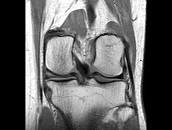

- 单项选择题男,29岁, 左膝关节有外伤史,膝关节疼痛, 活动受限,结合所提供的图像, 最可能的诊断是 ( )

B、前十字韧带撕裂

C、内侧半月板外周后角垂直撕裂

D、内侧半月板后角撕裂

E、后十字韧带撕裂